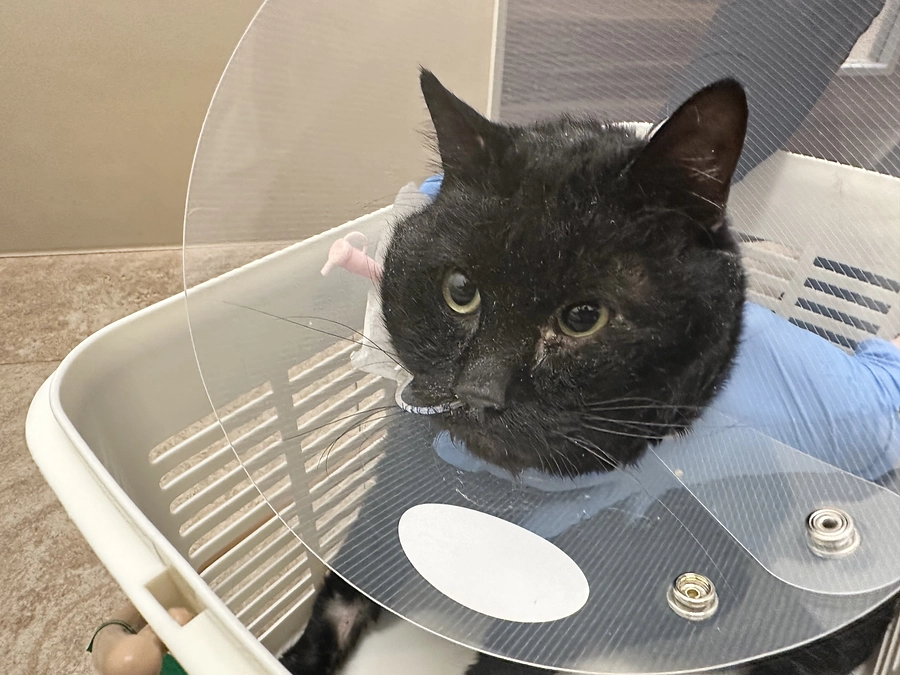

彦ちゃん、入院になりました

【 今日の彦ちゃん】

今日の彦ちゃん】

ご飯を食べなくなって5日目。

目がうつろで全く動きません。腹部全体が張っていて、朝からオシッコも出てません。

緊急を要すると思い『奈良動物医療センター』に受診しました。

採血とエコー検査の結果『急性膵炎』と診断され、入院になりました。

5日前から膵炎発症し、相当お腹が痛かったでしょうと。詳しい採血結果を待たないと確定診断できないそうですが、膵臓の周囲が肥厚しているので膵炎に間違いないということで治療開始して頂きました。

食事は食べれないので、鼻から管を通して流動食を注入して頂きます。

点滴をして頂いたお陰で脱水も少し改善され、しっかり目が開くようになりました。

やはりお腹が痛くて動けなかったんですね。可哀想なことをしました。朝まで待たずに受診して良かったです。

急激に悪化した場合、命の危険があるらしく予断を許さない状況ですが、彦ちゃんは強い子なので頑張ってくれると信じてます✨

昨夜23時に受診して、深夜2時半に帰宅しました。